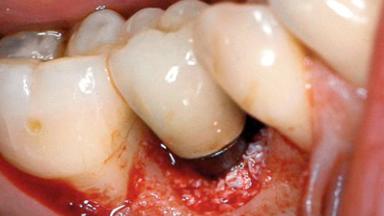

Peri-implantitis Modified by Submucosal Excess of Cement: Regenerative Peri-implantitis Therapy and Six-year Follow-up

A 30-year-old female patient was referred to the Department of Periodontology of the University of Bern, Switzerland, by a dentist in private practice. Tooth 45 had been congenitally missing and had been replaced with a titanium implant three years prior to the first visit at the Department of Periodontology. The tissue level implant had a diameter of 4.1 mm, a length of 12 mm, and a sandblasted and acid-etched (SLA) surface (Straumann® Dental Implant System; Institut Straumann AG, Basel, Switzerland). The metal-ceramic crown on implant 45 had been cemented permanently. Implant 45 had been diagnosed with peri-implantitis by the referring dentist in the course of regular supportive care.